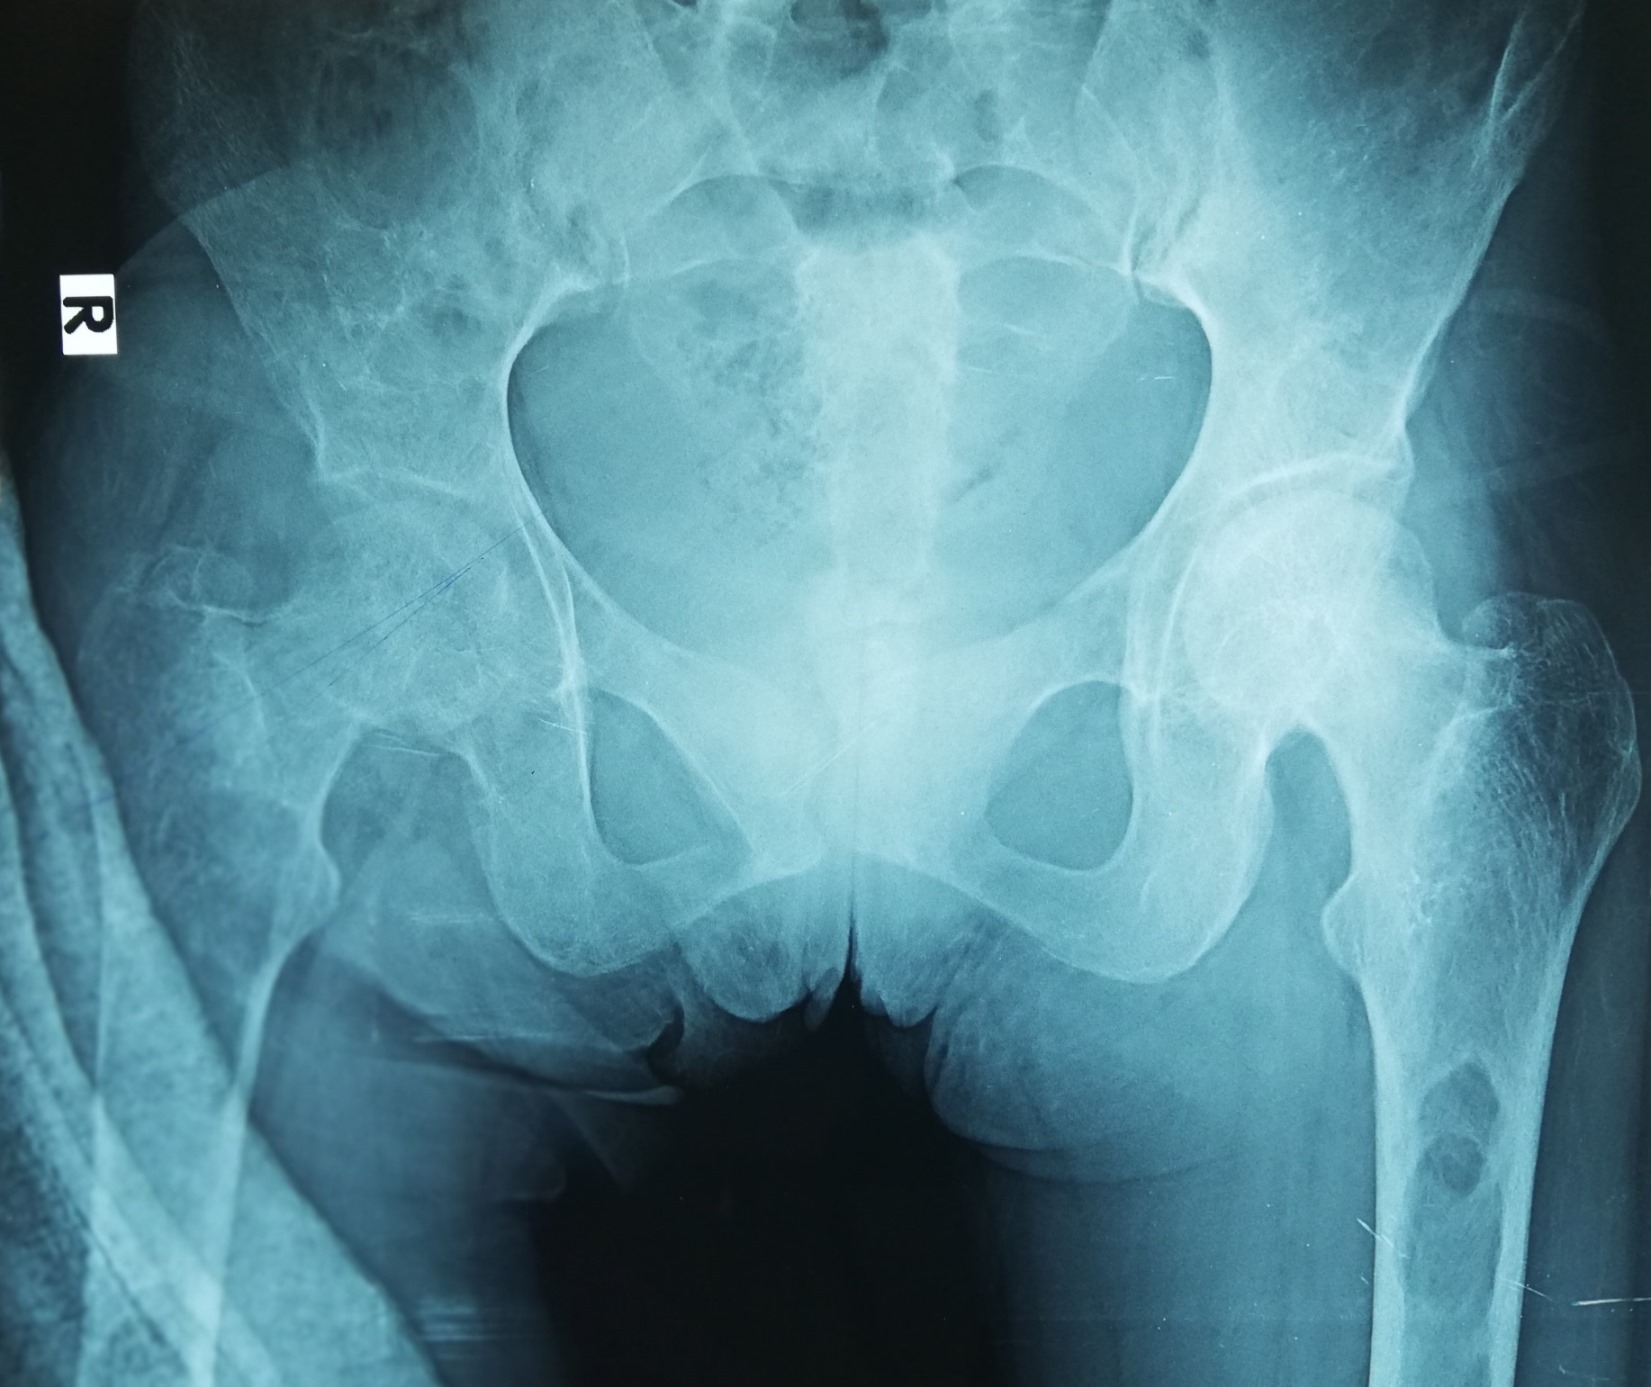

Radiology description

- Plain radiograph: well defined, purely lytic lesions that provoke little reactive bone; the cortex may be thinned and expanded but will not be penetrated (AJR Am J Roentgenol 1993;160:752)

- CT: attenuation values will be in the range of blood and fibrous tissue (Radiol Case Rep 2021;16:2482)

- Angiography (DSA): lesions are usually hypervascular (AJR Am J Roentgenol 1993;160:752)

- MRI: appearance depends on the relative proportion of its components; the lesions, therefore, may be solid, cystic or mixed (Skeletal Radiol 2011;40:205)

- Solid components are intermediate to low intensity on T1 and T2 weighted images, while the cystic components are hyperintense on T2 weighted images and may have fluid-fluid levels

- T1 C+ (Gd): there can be enhancement of the solid component and septa

- Nuclear medicine: bone scan often shows intense uptake (AJR Am J Roentgenol 1993;160:752)